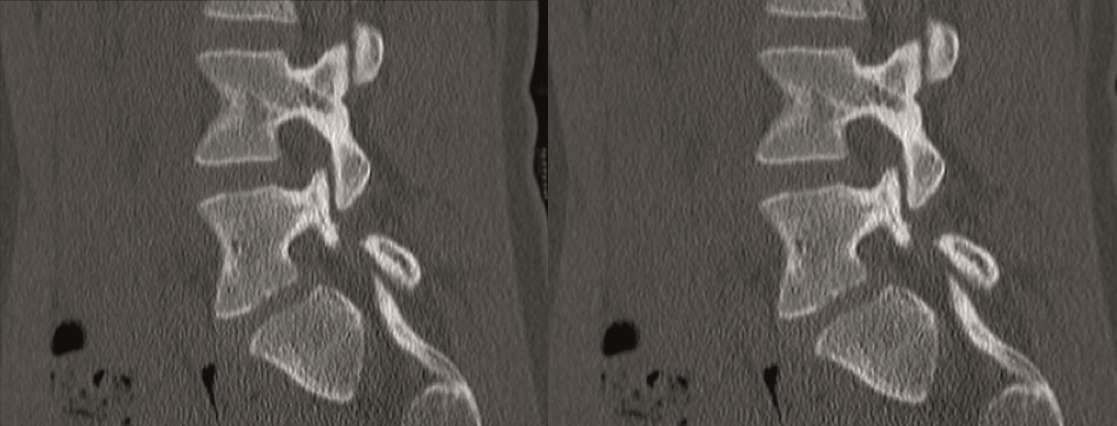

The CT showed bilateral L5 spondylolysis with grade I spondylolisthesis (Fig 10).

The patient underwent minimal access L5/S1 anterior interbody fusion with BMP followed by minimally invasive Matrix percutanous screw fixation (Fig 11).